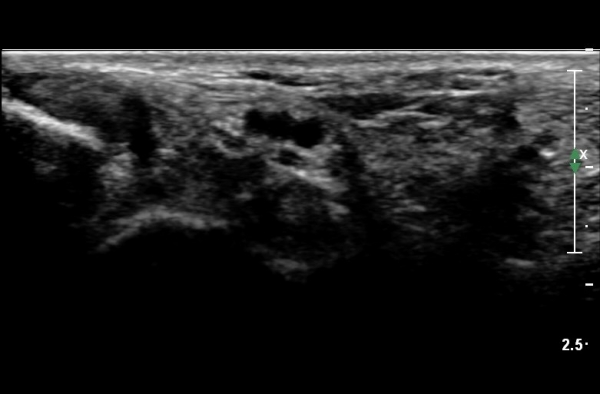

ŽÃËÀÚ¸¦ Á¶±Ý ´õ À̵¿ÇÏ´Ï ³¶Á¾ÀÌ ¿ÜÃøÁ·Àú½Å°æ Ç¥ÃþÀ¸·Î À§Ä¡ÇÑ´Ù. ½Å°æÀÇ ½ÉÃþ¿¡¼­´Â

±ä¾öÁö±¼°î°ÇÀÌ º¸ÀδÙ(»çÁø 4, 5).